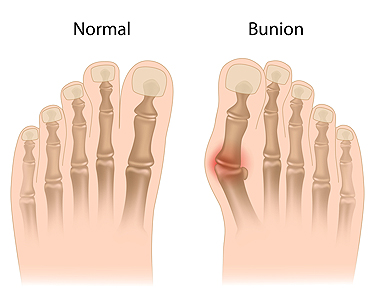

Understanding the Origins and Telltale Signs of a Bunion

Bunions, a prevalent foot condition, can cast a shadow on even the most graceful strides. A bunion, or hallux valgus, emerges when the joint at the base of the big toe shifts out of alignment, causing the toe to lean toward the other toes. The reasons why bunions may develop can vary, often stemming from genetic predisposition. Additionally, wearing ill-fitting footwear that squeezes the toes, or conditions that impact foot mechanics may lead to getting a bunion. The symptoms manifest as a bony bump at the base of the big toe, accompanied by pain, swelling, and redness. As the condition progresses, the affected toe may cross over or under the adjacent toe, causing discomfort and it can be difficult to find comfortable shoes. Recognizing the definition, causes, and symptoms of bunions is crucial in seeking the correct treatment. If you have a bunion, it is suggested that you consult with a podiatrist who can guide you toward the relief and treatment options that are best for you.

If you are suffering from bunion pain, contact one of our podiatrists of Mt Rose Foot & Ankle Specialists. Our doctors can provide the care you need to keep you pain-free and on your feet.

What Is a Bunion?

Bunions are painful bony bumps that usually develop on the inside of the foot at the joint of the big toe. As the deformity increases over time, it may become painful to walk and wear shoes. Women are more likely to exacerbate existing bunions since they often wear tight, narrow shoes that shift their toes together. Bunion pain can be relieved by wearing wider shoes with enough room for the toes.

Causes

- Genetics – some people inherit feet that are more prone to bunion development

- Inflammatory Conditions - rheumatoid arthritis and polio may cause bunion development

Symptoms

- Redness and inflammation

- Pain and tenderness

- Callus or corns on the bump

- Restricted motion in the big toe

In order to diagnose your bunion, your podiatrist may ask about your medical history, symptoms, and general health. Your doctor might also order an x-ray to take a closer look at your feet. Nonsurgical treatment options include orthotics, padding, icing, changes in footwear, and medication. If nonsurgical treatments don’t alleviate your bunion pain, surgery may be necessary.

If you have any questions, please feel free to contact our office located in Reno, NV . We offer the newest diagnostic and treatment technologies for all your foot care needs.